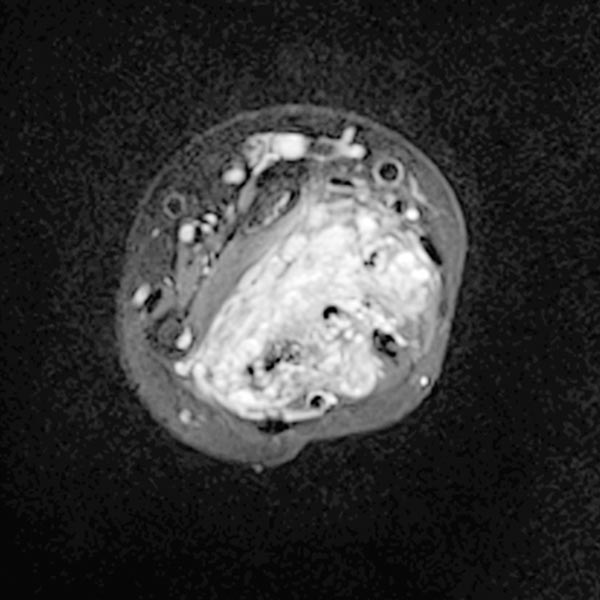

Axial T1-weighted, fat-suppressed contrast-enhanced sequence of the mid-forearm.

The venous malformation accumulates contrast within the involved muscle.

However, the vascular lumina of the venous malformation are relatively small, and no major tubular portions are found.